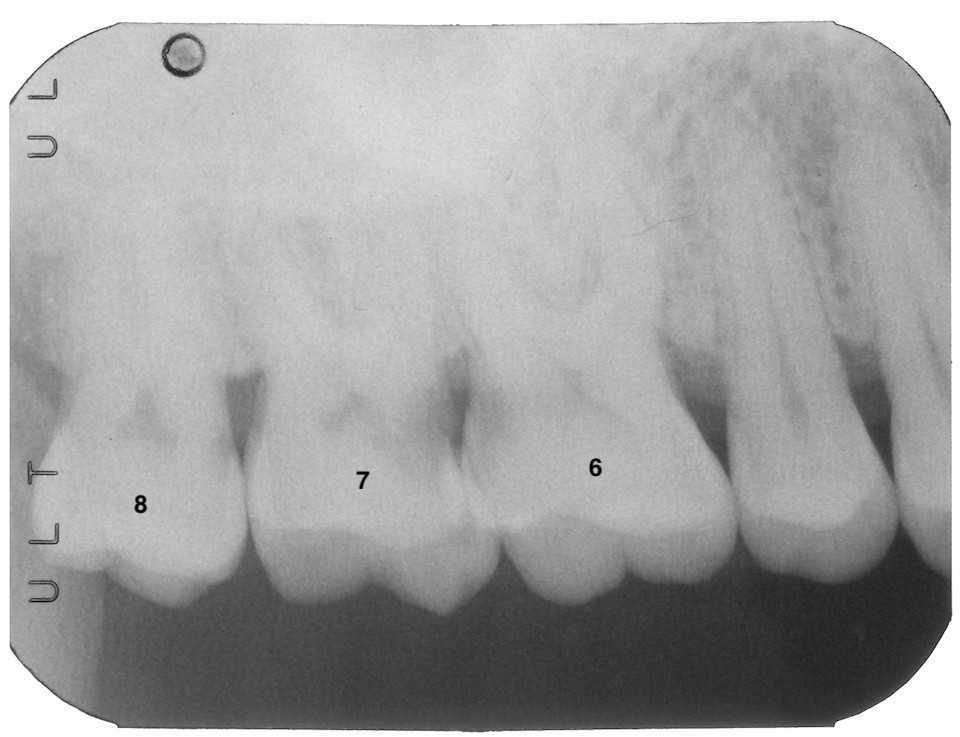

40代男性、右上7、咬合性外傷(食いしばり)、近心隣接面カリエス、自発痛++自治体職員で今回の選挙で駆り出され、痛くて眠れないほどなんだが、歯医者に行く時間も取れなかった。。この方、食いしばりがひどく、隣接面クラックから虫歯になるタイプだ。表面からはよく見えないので、気が付いたら深く虫歯が進行している。レントゲン写真では7番は歯髄に虫歯が達しているように見える。6番の遠心にもまだ症状の出ていない虫歯が見える。8番のDEジャンクションにも虫歯が始まっている。次回は6番の処置だが、7番の処置後に抗生剤を処方した。これで治らない時は再度露髄させて処置をする。強調しておくが、基本麻酔は使わない。患者の痛みは重要なセンサーになる。痛みが出てきたらそれ以上削る必要はないと考える。今日は痛くなっている7番からの処置だ。ちょっとだけ虫歯の穴が見えるが内部に大きく広がっている。歯科衛生士のSPT時にも見逃してしまう。咬合面からは見えない。歯肉縁下なので、辺縁隆線を大きく削除しないと虫歯が見えない。赤い部分は露髄しているところ。止血を確認して3MIX+α-TCPで直覆する。α-TCPが硬化したらCR:ダイレクトボンディングでフィニシングラインから積み上げていく。ストリップスも使わずどうやってCR充填するのか一般の歯科医師には分からないかもしれないが、ま、やればできるということは分かると思う。ストリップスを使う方が難しいということははっきりしている。デンタルフロスが入ることを確認して終わる。